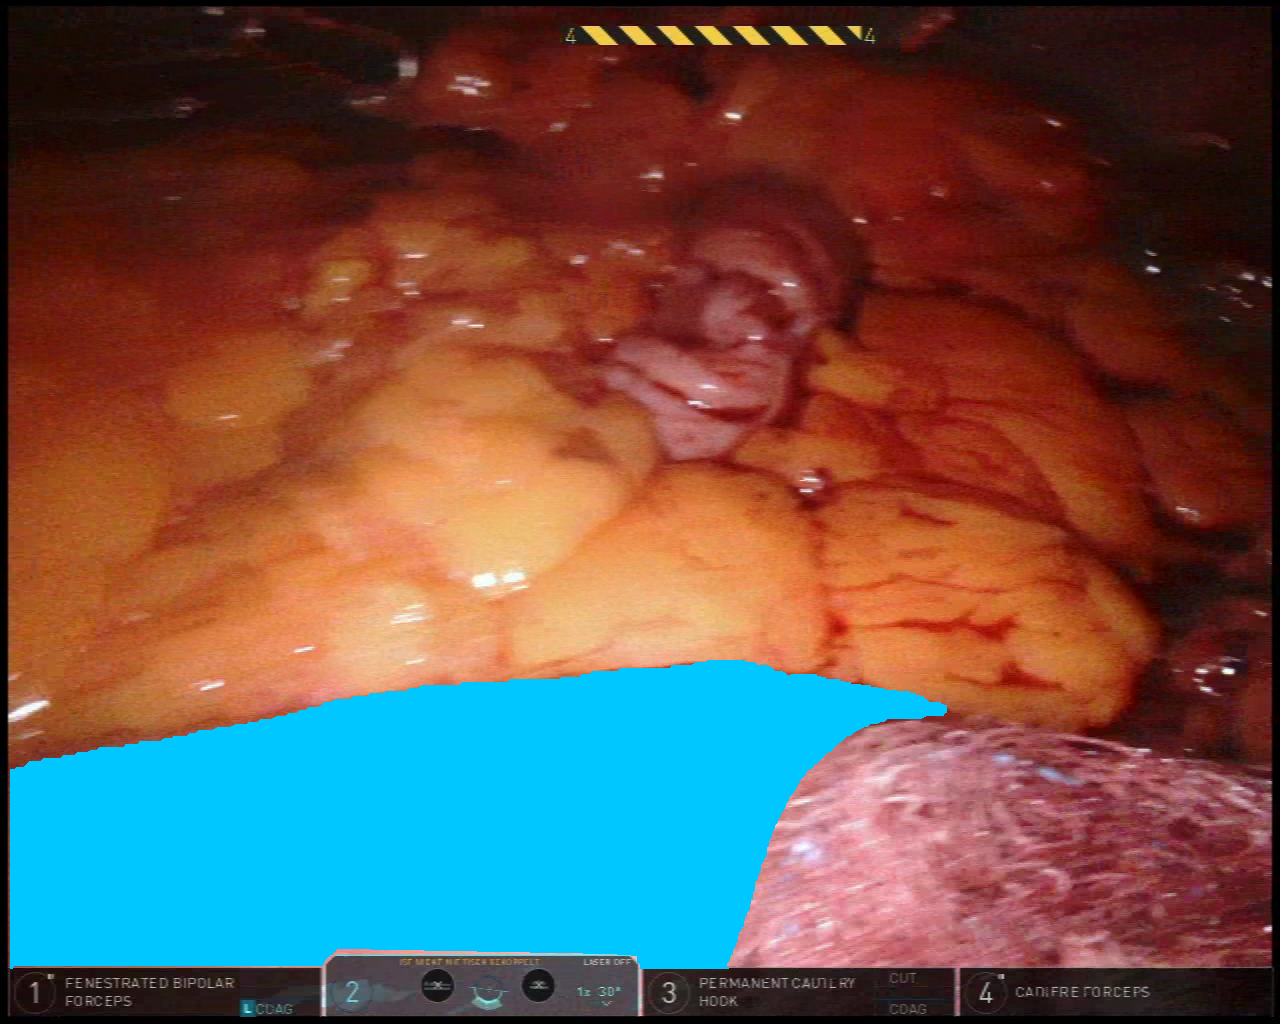

While the application of our proposed methodological approach to spectral imaging data represents our main focus, we also demonstrate the capability of our method in a non-spectral imaging dataset. More specifically, we make use of an RGB laparoscopic dataset that shares many similarities in terms of anatomical content and annotation style.

The Dresden Surgical Anatomy Dataset (DSAD[10] comprises 13195131951319513195 laparoscopic images from 32323232 patients of robot-assisted anterior rectal resections or rectal extirpation surgeries. Images provided in the dataset were extracted from the video and were stored in PNG format at a resolution of 1920×1080192010801920\times 10801920 × 1080. The annotation of 11111111 abdominal organs provided pixel-wise segmentation with multiple inclusion criteria for anatomical structures, resulting in sparsely annotated images across the dataset. The majority of annotations in this dataset only account for a single organ per image. However, a subset of the data is associated with multi-organ segmentation for all 11111111 anatomical structures. This includes a total of 1430143014301430 images in 32323232 patients.